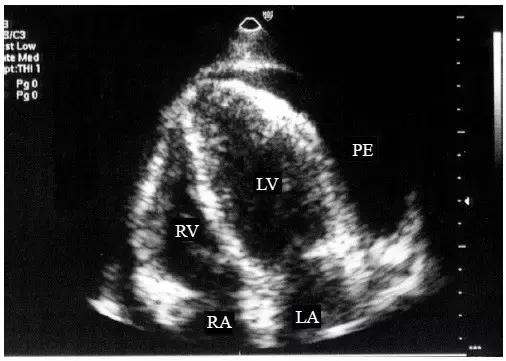

【中量心包积液】

左心室后壁心包腔内液体增多,心尖部也可探及液性暗区,但液性暗区不越过二尖瓣环,未抵达左心房的后方,右心室前壁液性暗区宽度<10mm(图2)。

图2 中量心包积液的二维超声心动图表现

左心室后壁和右心室前壁心包腔内均见液性暗区